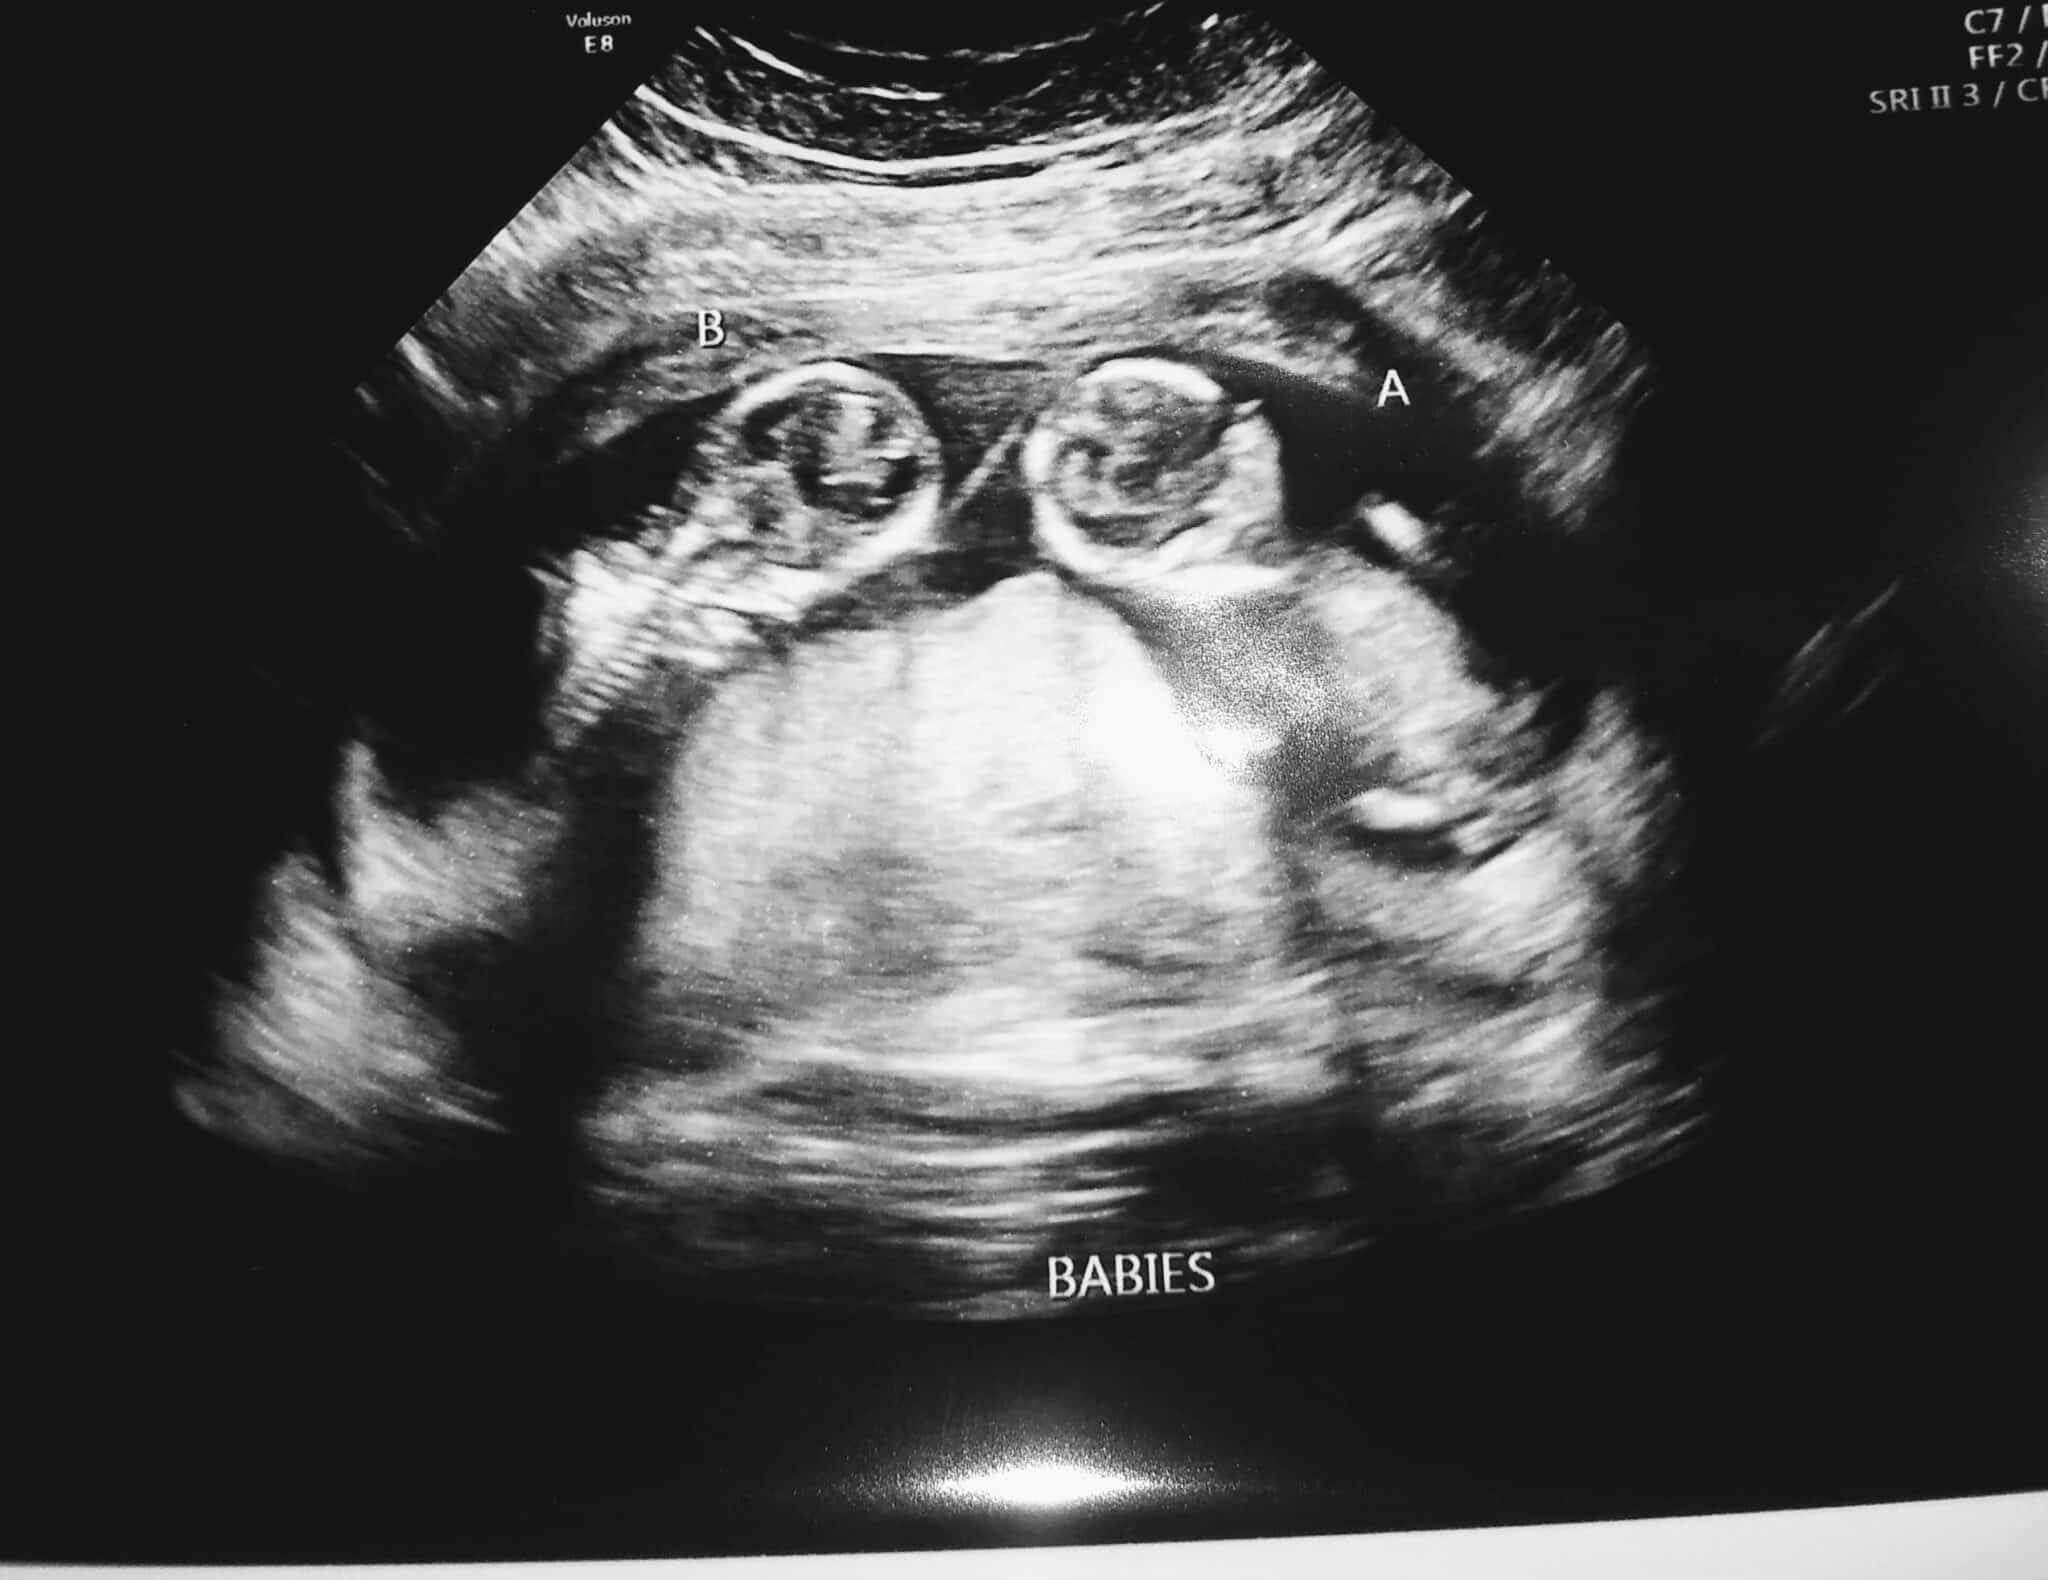

- Ultrasound Photos at 13 Weeks Pregnant With Twin

Ultrasound Photos at 13 Weeks Pregnant With Twin